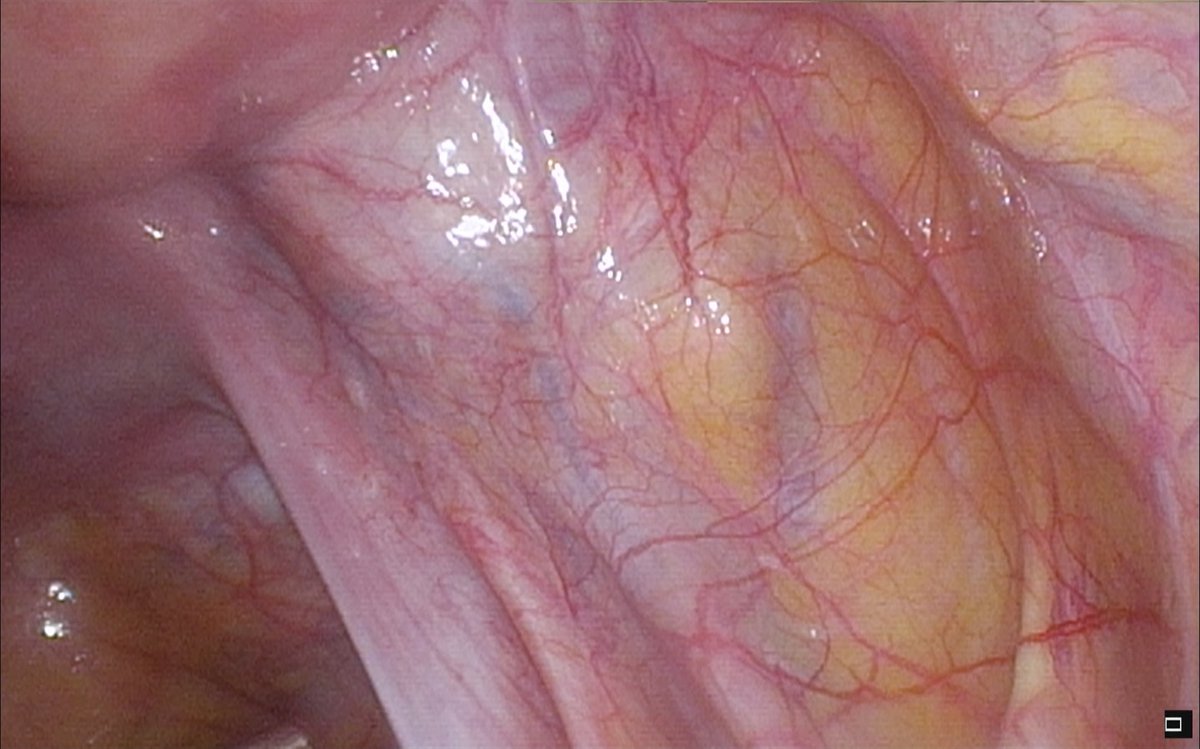

Dear Ob/Gyn, It's #EndometriosisAwarenessMonth. You've got a busy schedule, two more cases this morning, a full PM clinic and a social commitment at 5:30. You see this on the screen. Be honest with yourself. Do you see #endometriosis? Yes or no?